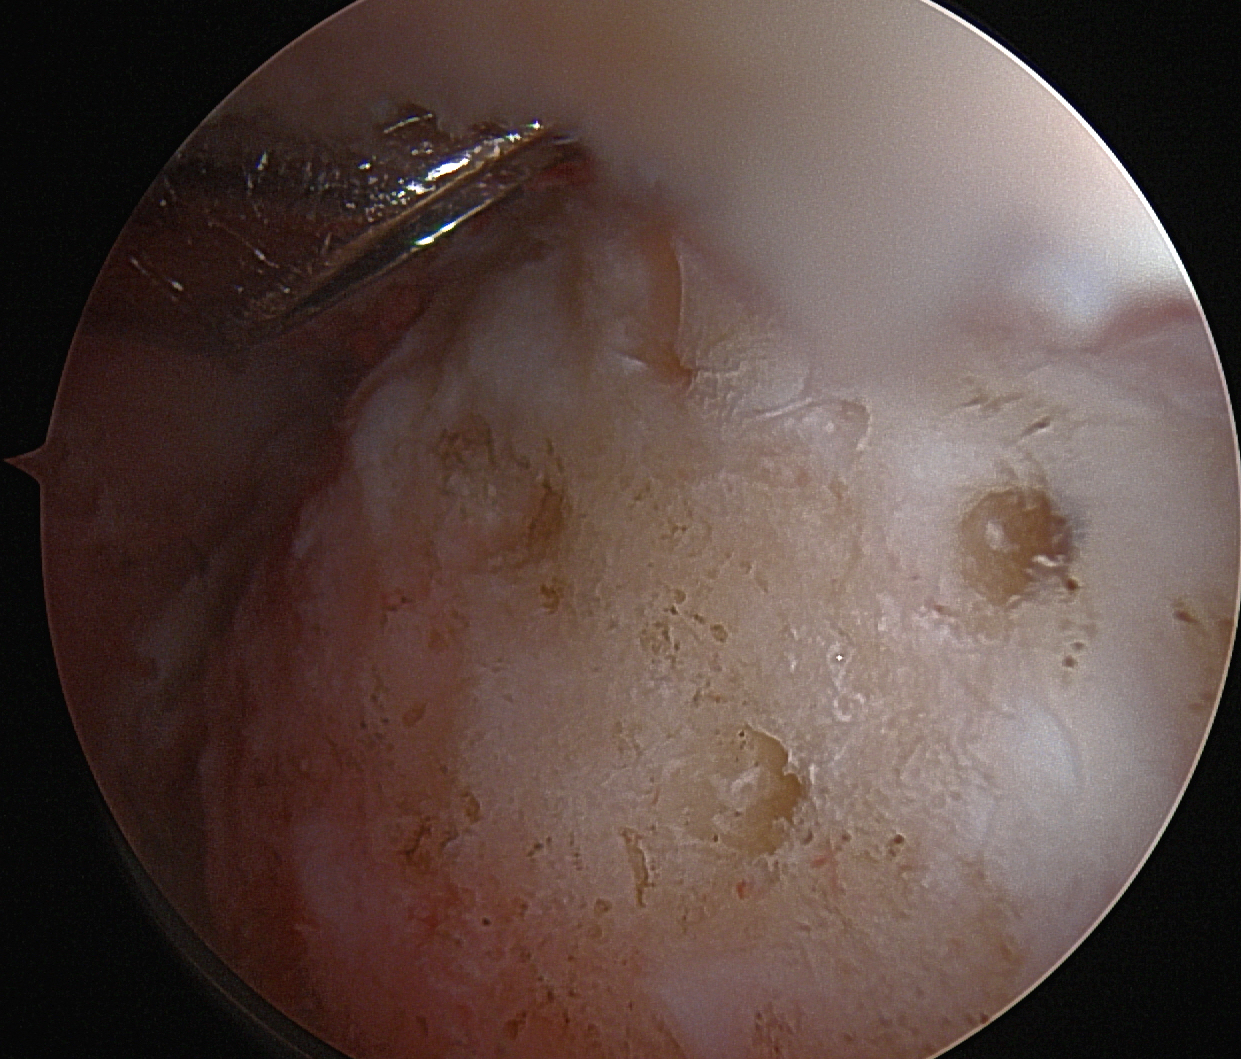

Arthroscopic multiple small drill holes techniques

Technique

- hip arthroscopy

- central compartment

- identify head neck junction

- multiple 1.5 mm drill holes into lesion in femoral head

- +/- BMAC

- retrospective study of CD versus multiple small drill holes

- 98 hips

- at 6 months better hip scores with multiple small drill holes